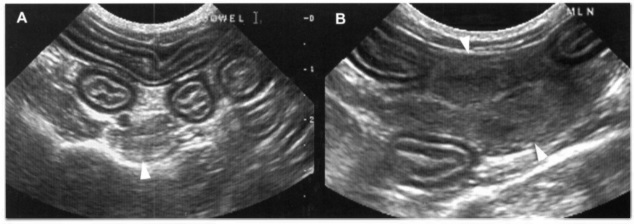

Лимфома ЖКТ поражает как часть стенки кишечника (Рис 1), вызывая локальное утолщение с потерей слоистости, так и целый одел ЖКТ на обширном протяжении без изменения слоев стенки (Рис 2).

РИС 1. Лимфома кишечника. Ультразвуковое изображение в продольной плоскости сканирования (А) и соответствующее ему схематичное изображение (В) участка кишечника кошки с лимфомой. Стенка кишечника утолщена по всей окружности (1 см толщиной) (показано курсорами). Слои стенки в левой части кишки еще просматриваются, но линия каждого слоя уже прерывистая. Слизистый слой значительно толще, чем в норме, что позволяет предположить идиопатическую гипертрофию или гиперплазию. В правой части изображения стенка кишечника значительно толще, в области расположения опухоли дифференциация слоев полностью нарушена. На схематичном рисунке стрелка указывает на место перехода нормальной стенки в участок с полным нарушением дифференциации слоев. L - просвет кишечника. Bowel – кишечник.